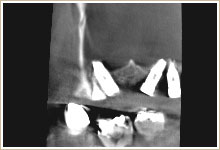

パノラマレントゲンの一部分です。骨の中にインプラントが埋まっているように見えます。

ところが、CTの正面からのスライス画像をみると、一部が骨に埋まっていないことが分かります。

上記と同様に上顎の奥にインプラントが入っています。

CTの正面からのスライス画像です。インプラントが顎骨の中にしっかり埋まっているのがわかります。